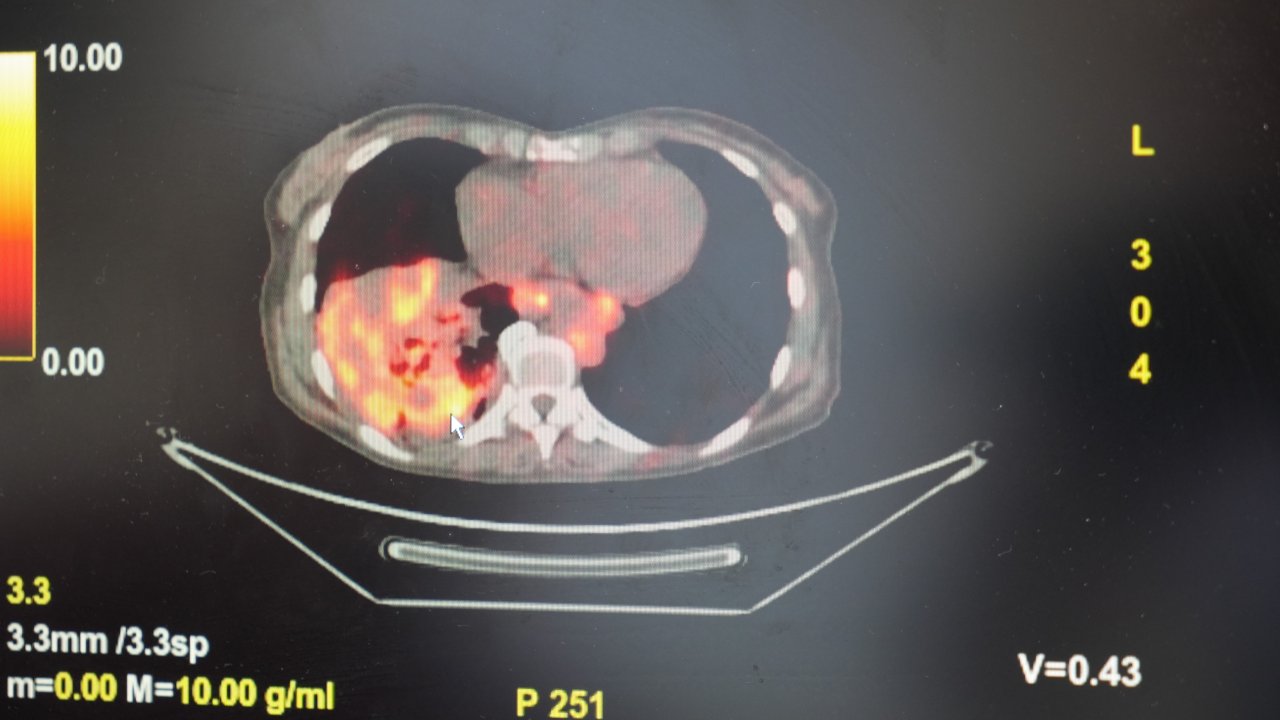

’Sigarasız akciğer kanseri’ vakalarında dikkat çeken artış